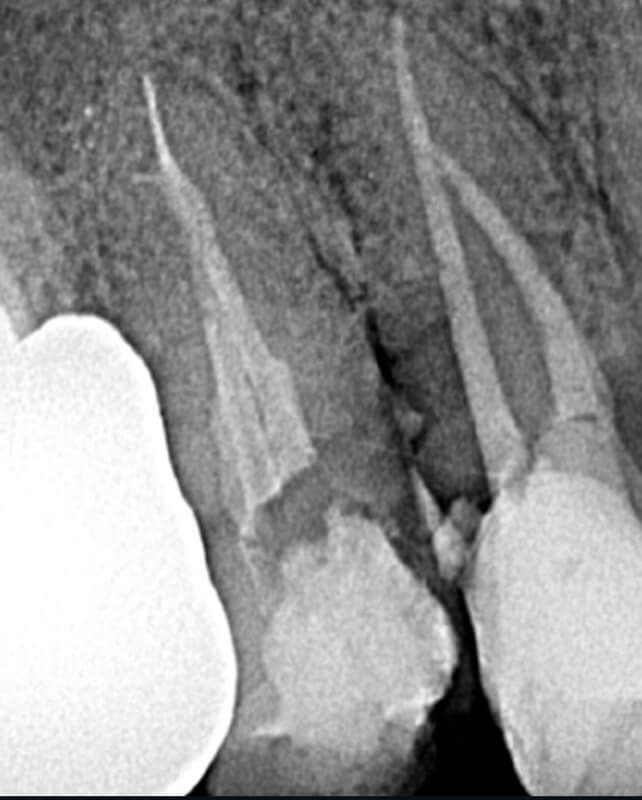

Endodonția este o ramură esențială a stomatologiei, axată pe diagnosticarea, prevenirea și tratamentul afecțiunilor pulpei dentare și a țesuturilor periapicale. Această specialitate joacă un rol crucial în salvarea dinților naturali, evitând extracțiile și menținând sănătatea orală pe termen lung. Prin tehnici avansate și echipamente de ultimă generație, endodonția asigură tratamente precise și eficiente, contribuind la redarea sănătății și funcționalității dinților într-un mod durabil și predictibil.

Tratamentele corecte reduc riscul de infecții și complicații viitoare.